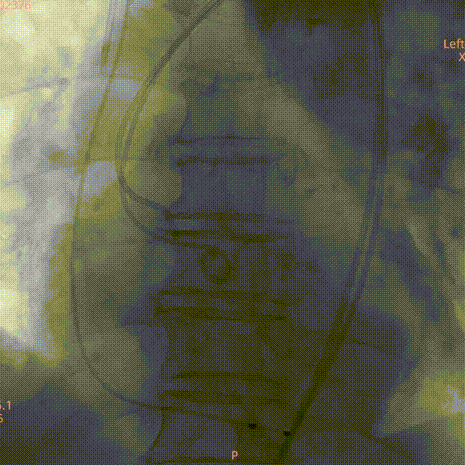

参考术前CT测量值,调整瓣膜至释放前最佳高度,缓慢释放近1/3长度时复查主动脉根部造影,确认瓣膜高度适合,临时起搏180次/分,以80:20比例23±1mL快速释放瓣膜至瓣膜工作区完全打开,于标准位置释放瓣膜;

复查造影提示瓣膜固定良好,形态尚可,未见明显反流;复查超声提示瓣膜功能正常,平均跨瓣压差下降至5.01mmHg,未见明显瓣周漏;最后退出鞘管,缝合血管。